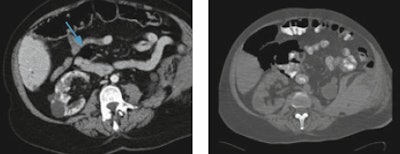

The main cause of missed injuries, such as pancreatic and diaphragmatic lesions, bladder rupture, and pseudoaneurysms, is the presence of multiple more evident injuries, such as solid organ lesions, that become the focus of attention.

"Bowel injuries, for example, are often missed in CT examinations because in polytrauma patients some specific bowel findings can be misdiagnosed, such as the presence of free small air collections misinterpreted as normal intraluminal air," Basilico noted.

Radiologists can overcome misdiagnosis by routinely using lung or bone window settings that help differentiate fat from air or multiplanar reconstructions, useful in vascular injuries and skeletal lesions. Moreover, a specific CT protocol for trauma patients, including unenhanced and multiphasic contrast-enhanced CT and, when necessary, a CT cystogram, will help radiologists detect an intra- and extraperitoneal bladder rupture in a case of multiple pelvic fractures, for example.